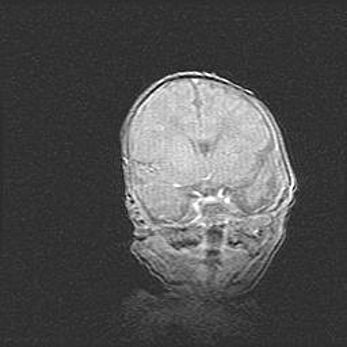

Церебральная ишемия II.

Возраст: 5 дней

Вес: 3400 г

Пол: женский

Окружность головы: 35 см

Срок гестации: 39 недель

Церебральная ишемия – это заболевание, характеризующееся недостаточностью (гипоксией) либо полным прекращением (аноксией) снабжения мозга кислородом по причине закупорки одного или нескольких сосудов. Это приводит к  что метаболическим расстройствам различной степени тяжести в тканях головного мозга, развитию коагуляционных некрозов и гибели нейронов.